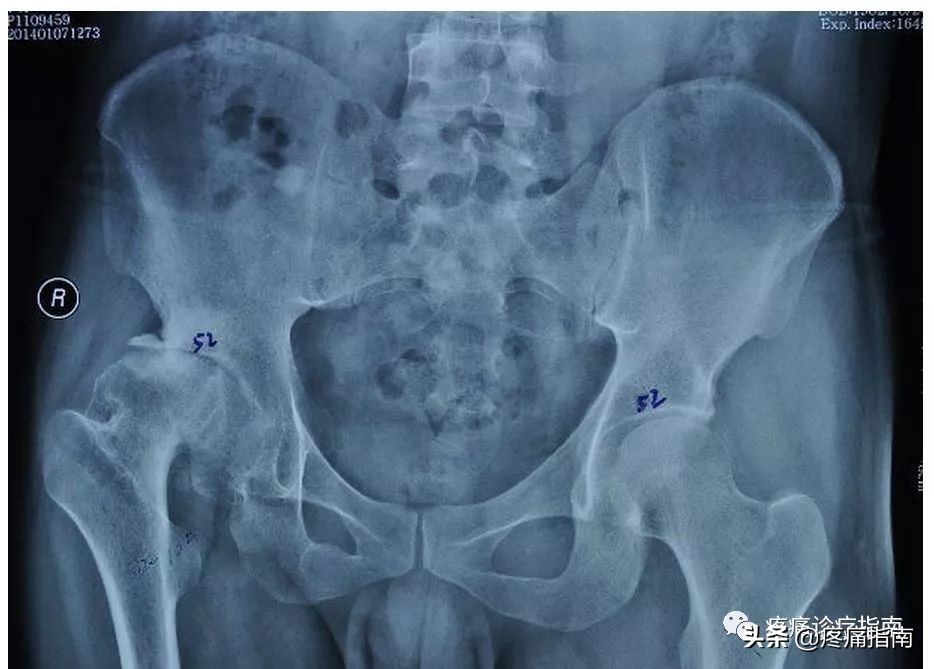

8.影像检查

X线摄片为骨性关节炎的常规检查,早期多正常,中晚期可见关节间隙不对称狭窄,关节面下骨硬化和变形,关节边缘骨赘形成及关节面下囊肿和关节腔游离体。根据Kellgren和Lawrecne的放射学诊断标准,骨性关节炎分为5级。0级正常。I级关节间隙可疑变窄,可能有骨赘。II级有明显的骨赘,关节间隙轻度变窄。III级中等量骨赘,关节间隙变窄较明确,软骨下骨质轻度硬化改变,范围较小。IV级大量骨赘形成,可波及软骨面,关节间隙明显变窄,硬化改变极为明显,关节肥大及明显畸形。

④髋关节骨关节炎临床及放射学诊断标准:近1个月内大多数时间有髋关节疼痛;血沉≤20mm/h;X线片示股骨和 (或)髋臼有骨赘;X线片示髋关节间隙狭窄。满足①+②+③条,或①+②+④条或①+③+④条者,可诊断为髋关节骨关节炎。